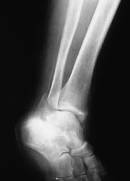

【スライド6】

確認:

翌日整復が良好に治まっているか確認するため近医にてX線撮影を行うこととした。

このスライドがそのレントゲン写真です。

2 36日 (2日目)

患者に自発痛はなく全身症状の経過は良好でしたが、X線診断の結果、整復が不十分と判断し、前日同様の再徒手整復を行いました。骨折部の整復状況を触診にて確認し、問題ないと判断した後、再度前日同様に固定をしました。